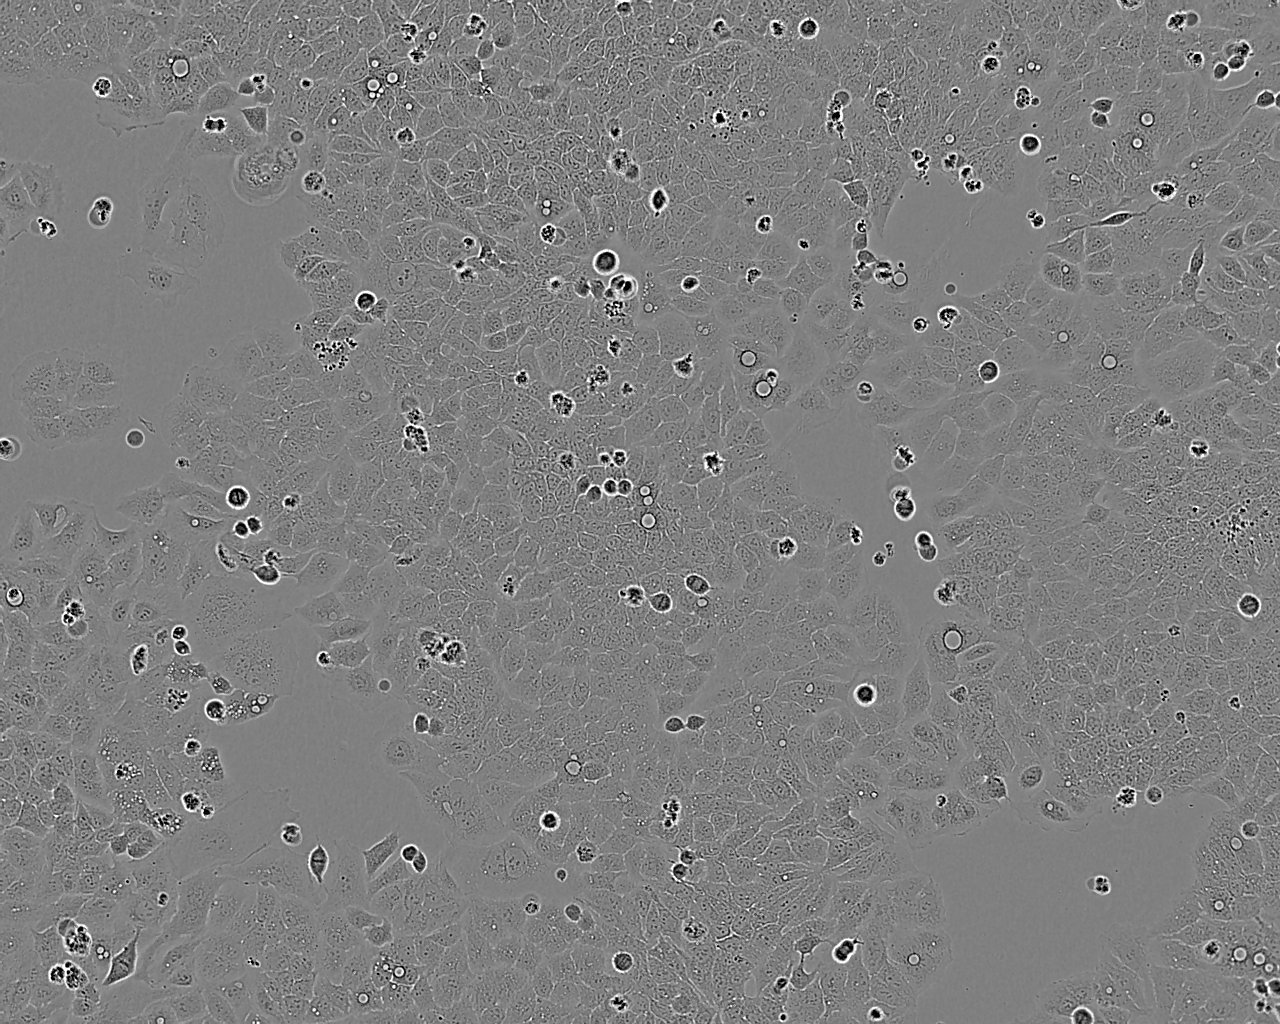

细胞形态:上皮细胞样

细胞生长:贴壁

细胞生长特性:贴壁或悬浮,详见细胞说明书部分